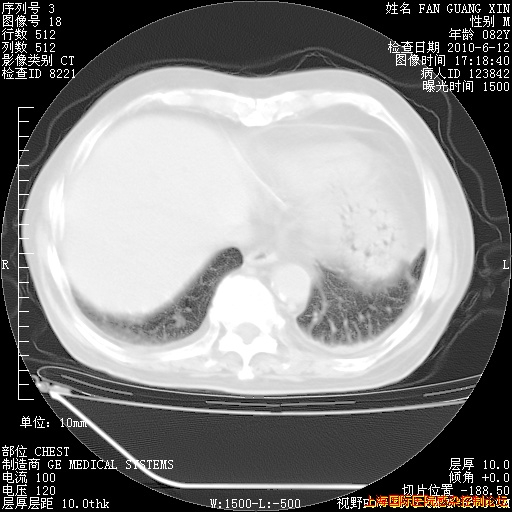

补发6月12日肺部CT肺窗

6月12日肺窗